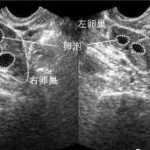

从医学角度看,胎儿停育是指胚胎发育到一个阶段,但由于某些因素导致早期胎儿死亡而停止发育的现象。经过一系列的过程,受精卵出现异常,可能是男性精子质量的原因,另一方面是胚胎本身的原因,第三个可能是染色体的原因。只有逐一了解,才能知道你的具体原因,给予专业的试管婴儿治疗。胎儿停育的原因是什么?1.精卵质量:影响受精卵质量的主要因素是精子的密度、形态、活性和质量。如果女性月经周期过短,说明卵泡发育不成熟;多囊卵巢综合征、月经周期延迟、避孕药、过度使用促排卵药物等。会导致女性卵子质量差。若精子与卵子结合质量差,很可能导致胎停。2.遗传因素:特别是对于老年妇女,如果孕妇或胎儿染色体在怀孕期间异常或遗传基因缺陷,这些情况将导致胎儿停产。因此,建议准备怀孕的夫妇必须进行染色体检查,这不仅可以有效避免胎儿停止,而且可以确保婴儿出生后的健康。3、子宫环境:如果女性子宫异常(如畸形、肿瘤等),会导致胎儿发育到一定大小时,因为子宫的实际情况会阻碍胎儿的发育,最终导致胎儿畸形、先天性发育不良或胎儿停止。4.激素分泌:女性在怀孕期间需要大量的孕酮和雌激素来支持胎儿的生长发育。如果怀孕期间体内激素分泌不足,很难支持胚胎发育,从而导致胎停。此外,黄体功能不全、内分泌紊乱等也是导致胎停的重要因素。多胎停育可选择第三代试管婴儿技术筛查染色体若出现多次胎停现象,不能再盲目自然受孕,建议选择试管婴儿助孕技术,避免因各种因素引起的胎停现象。对于受精卵的质量,我们可以选择质量最好的精子和卵子,实施单精子注射技术,使卵子完成受精过程。形成囊胚后,使用第三代试管婴儿PGS/PGD基因筛查技术可以识别囊胚的质量,全面筛查23对染色体,有效避免各种异常染色体疾病和家族遗传疾病。保证囊胚质量意味着保证婴儿出生后的健康。目前三代试管的医疗费用一般是810万,具体费用要看试管在哪里,结合生活费用才能知道。然而,绿桥建议,如果胎儿多次停止,不要自然怀孕,最终容易出现习惯性流产。此外,如果您对第三代体外受精有其他问题,您可以随时通过以下联系信息联系我们,绿桥将有专门的医疗团队评估您的身体状况,回答各种问题,并结合实际情况提出身体调理建议,帮助您可能提高试管成功率。